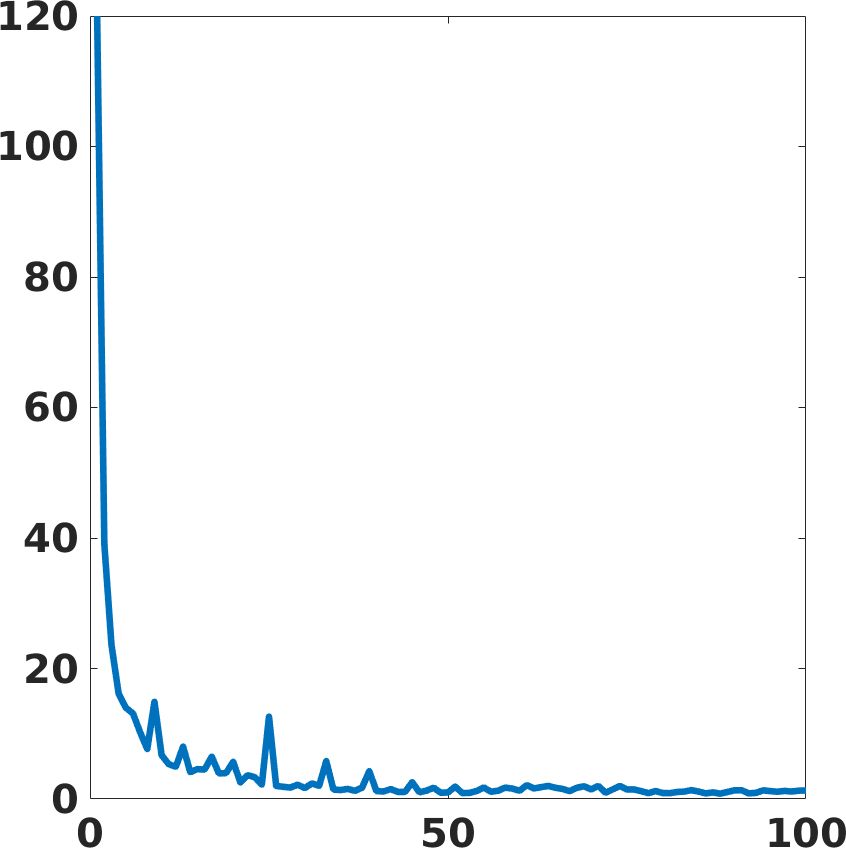

4.5 Execution time and computational cost

We define an HPC implementation of the proposed framework on the CINECA-Marconi100 cluster, exploiting both CPUs (IBM POWER9 AC922) and GPUs (NVIDIA Volta V100). We design a parallel and distributed implementation in TensorFlow2, and we train multiple networks with large data sets for the target medical application. To test the training phase of the learning-based networks in the HPC environment, we exploit 8 nodes, each one composed of 32 cores and 4 accelerators, for a theoretical computational performance of 260 TFLOPS, and 220 GB of memory per node. The parallel implementation of the deep learning framework and the high hardware performance reduce the computation time of the training phase by at least 100 orders less than a serial implementation on a standard workstation. Fig. 19 shows the training loss and validation PSNR. Both metrics show convergence property within 100 epochs iteration. In particular, the validation PSNR goes from a value of 41 to a value of 58 after 100 epochs.